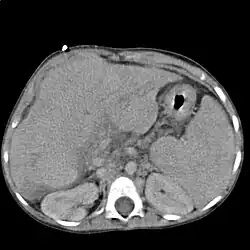

Im Ultraschall stellt sich die Leber inhomogen dar. Der Leberrand ist wellig, die Binnengefäße sind rarefiziert. Der Lobus caudatus kann vergrößert sein. Sehr gut können mit dem Ultraschall ein Aszites und eine Milzvergrößerung (Splenomegalie) erkannt werden. Eine verbesserte Form der Sonographie stellt der sogenannte Fibroscan, auch bekannt als transiente Elastografie, dar. Hiermit kann die Fibrosierung, also der Bindegewebsumbau, der Leber ermittelt werden, was ein sehr zuverlässiges Ergebnis zur Diagnosestellung liefert und zukünftig die Leberbiopsie (s. u.) ersetzen könnte. Mit der farbkodierten Doppler-Sonografie lassen sich in der Pfortader ein verminderter Fluss sowie in der Leberarterie ein erhöhter peripherer Widerstand messen.